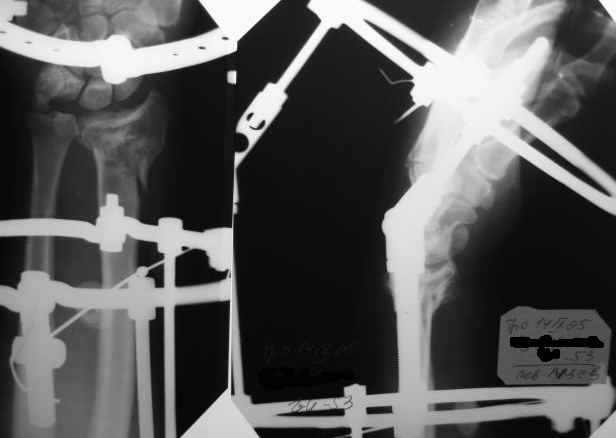

Спасибо, коллеги, за помощь в принятии решения. Остановились на АВФ, но в классической компоновке (3 секционный, замкнутые кольца). Снимки конечного результата в приложении.

Интраоперационно старались добиться более лучших взаимоотношений, но выяснилось (благо больной под региональной анестезией!), что у пациента был <перелом луча> с обеих сторон около 20 лет назад, движения на оперируемом суставе были несколько ограничены. Поэтому решили оставить так. К сожалению, снимков 20-ти летней давности не нашли. Планирую оставить внешнюю фиксацию на весь срок. Жду комментарии. С уважением, А.Минервин.

Все получилось хорошо, положение отломков более чем премлемое.

По рентген у луча "минус" вариант и это отрицательно будет высказываться на функции лечезапятсного сустава, т.е. у больного ограничение локтвеой девиации кисти.

Однако этого можно было предотвратит если бы ВЫ до остеосинтеза кисти придали локтевой девиации 25 градусов, одну спицу провели через диафиз первой пястный, вторую через вторую и третью пястные кости и вмонтировали на дисталоьное кольцо, тогда при должном дистракции.